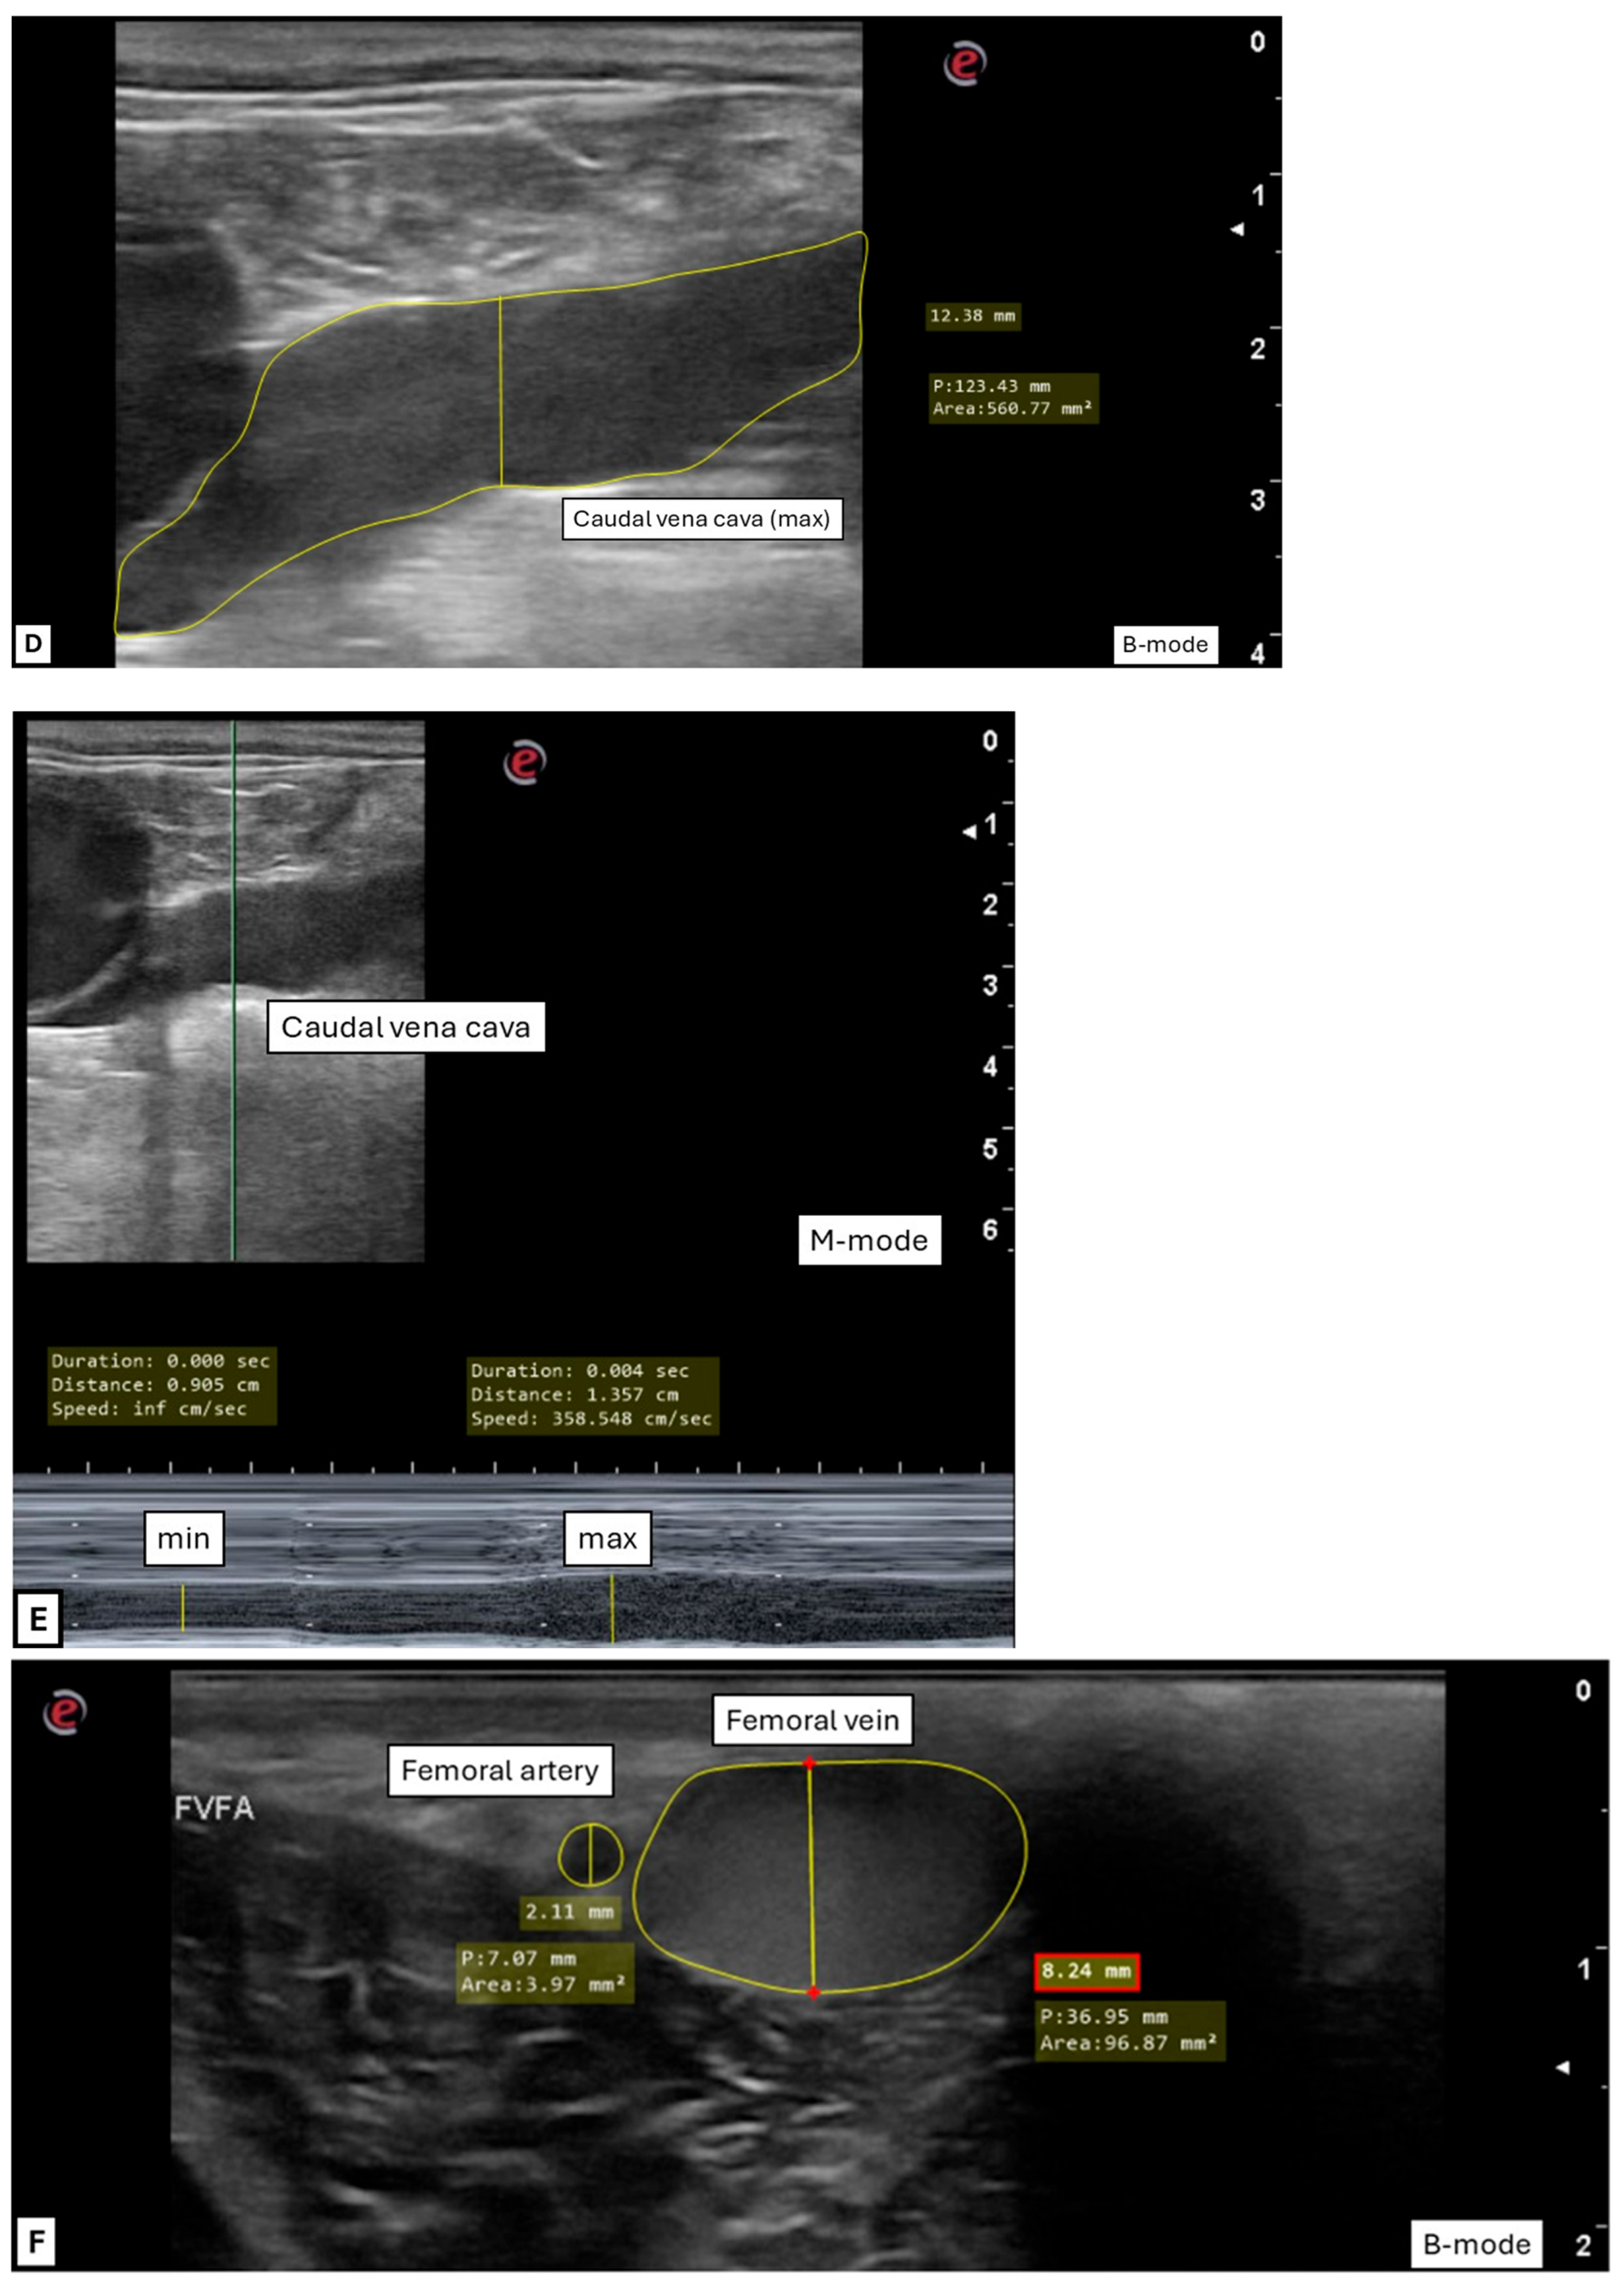

2.3.2. Transrectal Variables

2.3.3. Inguinal Variables

3.2. Transrectal Variables

3.3. Inguinal Variables